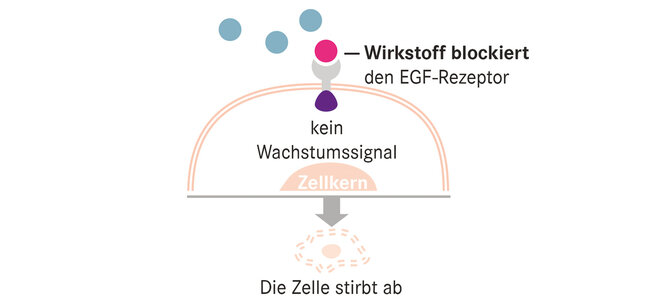

Bei der häufigsten Unterform des nicht kleinzelligen Lungenkrebses, dem Adenokarzinom, sind diese DNA-Umformungen für rund zwei Drittel aller Fälle verantwortlich. Steht die Ursache fest, ist auch der Weg zur Therapie nicht mehr weit. Für acht Treibermutationen sind bereits Medikamente zugelassen. Zu etlichen weiteren laufen Studien. Rund 40 Prozent der Adenokarzinome lassen sich bisher mit den „-tinib“ behandeln, auf das all diese Mittel enden. Doch fast alle der zielgerichteten Medikamente kommen erst in einem fortgeschrittenen Krankheitsstadium zum Einsatz, wenn klassische Therapien versagen. Eine Heilung ist dann nicht mehr möglich. Aber teils eine Lebensverlängerung.

Am besten untersucht ist dies für EGRF-Mutationen, Ursache für rund 15 Prozent der Adenokarzinome. Osimertinib, der neueste unter mehreren Wirkstoffen gegen diesen Typ, verlängerte die Zeit bis zum Fortschreiten der Krankheit auf 19 Monate; nach 18 Monaten lebten noch 83 Prozent der Patientinnen und Patienten.

„Erst wenn wir im Spätstadium Erfolge verzeichnen, folgen weitere Studien zur Wirksamkeit bei früheren Stadien und zu einem früheren Behandlungszeitpunkt“, sagt Professorin Annalen Bleckmann, Direktorin des Westdeutschen Tumorzentrum Netzwerkpartner Münster. Bei Osimertinib war eine solche Studie bereits erfolgreich. Direkt nach der Operation eingesetzt, waren 90 Prozent der Behandelten nach zwei Jahren noch krankheitsfrei, hingegen nur 44 Prozent in der Placebo-behandelten Vergleichsgruppe. Weitere Wirkstoffe für andere Genveränderungen sind auf einem ähnlichen Weg. Ob zuvor trotzdem noch eine Chemotherapie nötig ist, untersuchen ebenfalls derzeit noch laufende Studien.

Ohne Nebenwirkungen sind auch die zielgerichteten Medikamente nicht. Fast die Hälfte der Patientinnen und Patienten leidet an Durchfall, jede und jeder vierte bis fünfte unter einem Hautausschlag oder Juckreiz. Ernsteres kommt vor, aber selten: So erlitt in der oben genannten Studie je einer unter 337 Behandelten einen (nicht tödlichen) Herzinfarkt oder eine Thrombose.